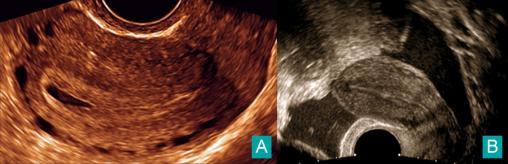

Charlotte Laplane, Claude d’Ercole (La Revue du Praticien) A. Pseudo-sac gestationnel.B. Épanchement du cul-de-sac de Douglas.